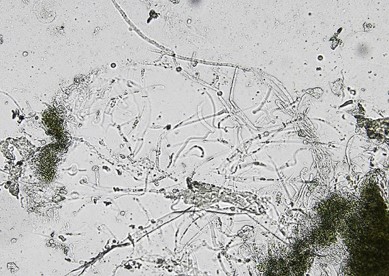

顕微鏡検査で胞子を伴う菌糸の存在を検出します。

皮膚、外鰓や鰭の損傷部にカビの胞子が付着し(小さな白点が見える程度)、次第に増殖して綿帽子状に多数の菌糸が広がります。最終的には組織内に侵入した菌糸によって表皮組織が崩壊し、寄生部位を出血させたり、壊死させます。皮膚の浸透圧差調節の破壊によって、全身性浮腫症候群が起こることもあります。